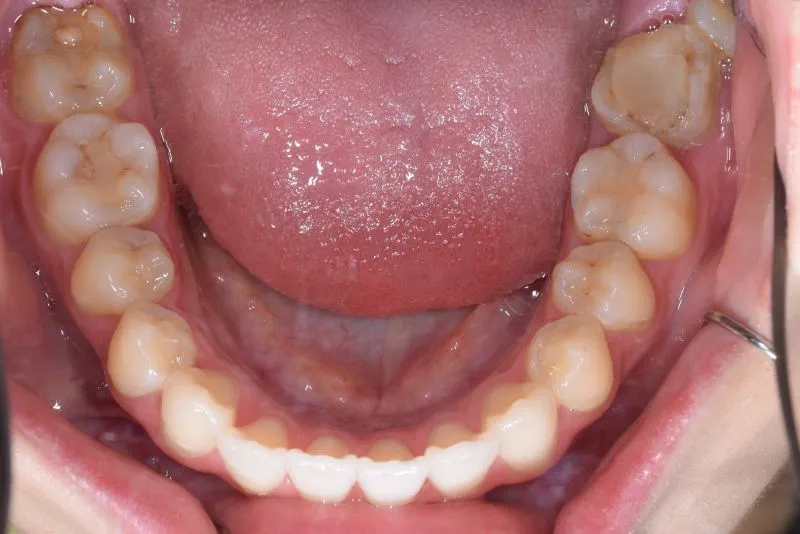

治療経過1

再治療の時は、上の歯は前から見えにくいオリジナル固定装置、下の歯はマルチブラケット装置を使用し、治療しました。

治療回数62回、1年6ヶ月の治療期間で矯正治療を終了しました。

前回の治療で歯の根っこの部分の位置を治していたので、全部前から付けるのではなく最低限見える装置で治せました。